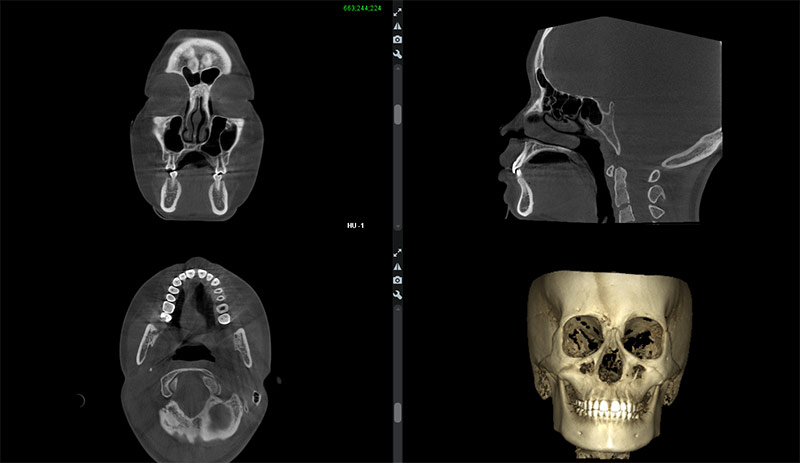

近年では、セファログラム以外にもCT撮影が診断に大きく携わっています。

CT

CTはセファログラムでは得られない、3次元的な情報を細部まで得ることができるので、レントゲン撮影のような平面では判断できない診断が可能となり、より的確な治療を提供できます。